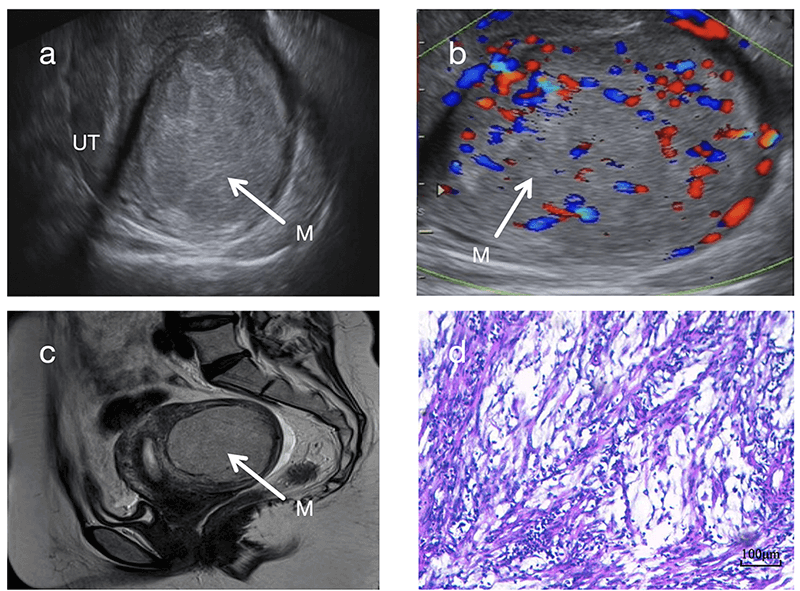

From the perspective of tumor size and growth characteristics, UIMT masses are often relatively large. The median maximum diameter of UIMT masses in this study was 6.9 cm, slightly larger than the 5 cm reported by Bai et al. [6]. Additionally, the color Doppler flow signals in this cohort were more abundant, suggesting that a rich vascular supply may contribute to tumor enlargement. Notably, the masses in Case 2 and Case 3 showed rapid growth over a short period, likely reflecting the biologically active proliferation nature of UIMTs. The combination of “rapid enlargement over a short period and abundant blood flow signals” should be regarded as an important diagnostic alert for UIMT. Recognition of this pattern may prevent clinicians from overlooking potentially borderline tumors that appear morphologically benign. Ultrasonographic evaluation revealed ill-defined margins in Cases 4 and 6, which corresponded pathologically to infiltrative growth into the surrounding smooth muscle. This finding highlights the diagnostic value of evaluating tumor margins during ultrasonography. Compared with typical uterine leiomyomas, UIMTs showed richer color Doppler flow signals (Fig. 2b,d). In particular, Cases 1 and 2 exhibited extremely abundant vascularity, forming a characteristic “colorful mosaic sign” (Fig. 1b, Fig. 2b).

Fig. 2.

Comparison of sonographic images between submucosal UIMT (Case 1) and typical submucosal uterine leiomyoma. (a) Sagittal ultrasonographic view of the submucosal UIMT mass. White arrows indicate the tumor masses. (b) CDFI showing abundant blood flow signals within the submucosal UIMT mass (Adler grade 3) with a “colorful mosaic sign”. (c) Sagittal ultrasound view of a typical submucosal uterine leiomyoma. White arrows indicate the tumor masses. (d) CDFI showing sparse blood flow signals in the typical submucosal uterine leiomyoma (Adler grade 1).

A key observation in this study was the “blurred halo sign”, identified as a typical ultrasonographic feature of UIMT. This sign is characterized by scattered strip-like or patchy hyperechoic areas within a hypoechoic background (Fig. 1a, Fig. 2a). It is clearly distinguishable from the “whorled pattern” typically observed in conventional leiomyomas (Fig. 2c). In leiomyomas, heterogeneous hypoechoic or isoechoic areas create whorled textures due to interwoven smooth muscle cells and connective tissue fibers. In contrast, UIMT lesions display more homogeneous, dense internal echoes. Its signal on magnetic resonance imaging (MRI) also appears relatively homogeneous (Fig. 1c), whereas leiomyomas generally show lower and more disorganized echogenicity (Fig. 2a,c). However, overlap in imaging features may occur when leiomyomas undergo degenerative changes, such as mixed echogenicity or cystic transformation [11]. In such instances, the diagnostic utility of the “blurred halo sign” when combined with abundant blood flow signals becomes even more prominent.